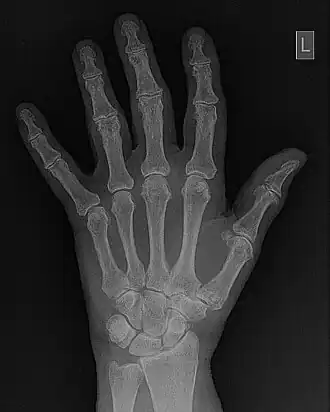

- Fourier filtering is illustrated in more detail in Figure 5.10. The wrist/hand radiograph of the Figure 5.6 is again used for this illustration. You might remember that its 2D FFT was discussed in an earlier chapter. The filter is shown in panel (c) of the figure in the form of a two-dimensional image. It can be seen that the image data is symmetrical around the centre (i.e.isotropic) where its pixel values are relatively low. Outside this central dark region, a halo of bright pixel values dominates the image as the pixel value trails off slowly towards the periphery. An amplitude profile through this image is shown in panel (d) to further illustrate the effect. The filter can be used to modify the 2D-FFT by multiplying it by the filter values, for instance, to form a filtered 2D-FFT - as shown in panel (e). The Inverse FFT (IFT) of this data is then reveals the filtered image - see panel (f). Given that certain spatial frequencies have been amplified while others have been suppressed with this type of filter, it is called a Bandpass filter.

DICOM-standard images contain what is called a header file which contains information regarding the patient, the examination and the image data - a section of one is shown in the following figure as an example. Note that in this case the image data refers to a hand/wrist image which is stored at a resolution of 2,920x2,920 pixels each of size 0.1 mm. In addition, default window display settings are shown. Furthermore, the form of image compression used can be included, i.e. whether lossless, which preserves the fidelity of image data, or lossy which degrades fidelity in the interest of image transfer speeds, for instance. Numerous other parameters can also be included in a header file.